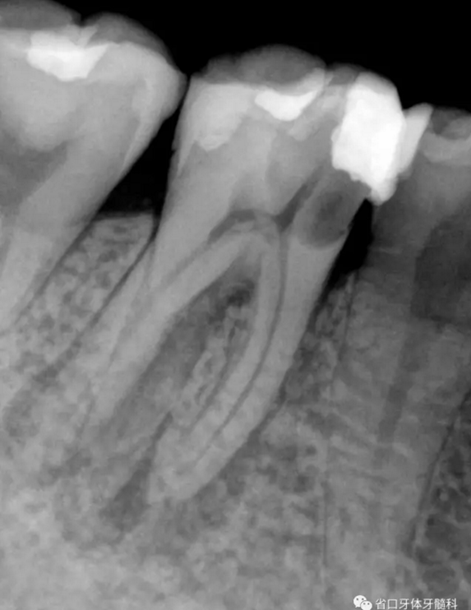

圖1 術前X線片:46/近中根面繼發(fā)齲,根尖周低密度影,遠中舌側(cè)根管影像模糊;根分叉低密度影,近中牙槽骨見少許角形吸收。